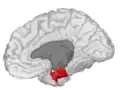

-

Entorhinal cortex, shown in the right cerebral hemisphere.